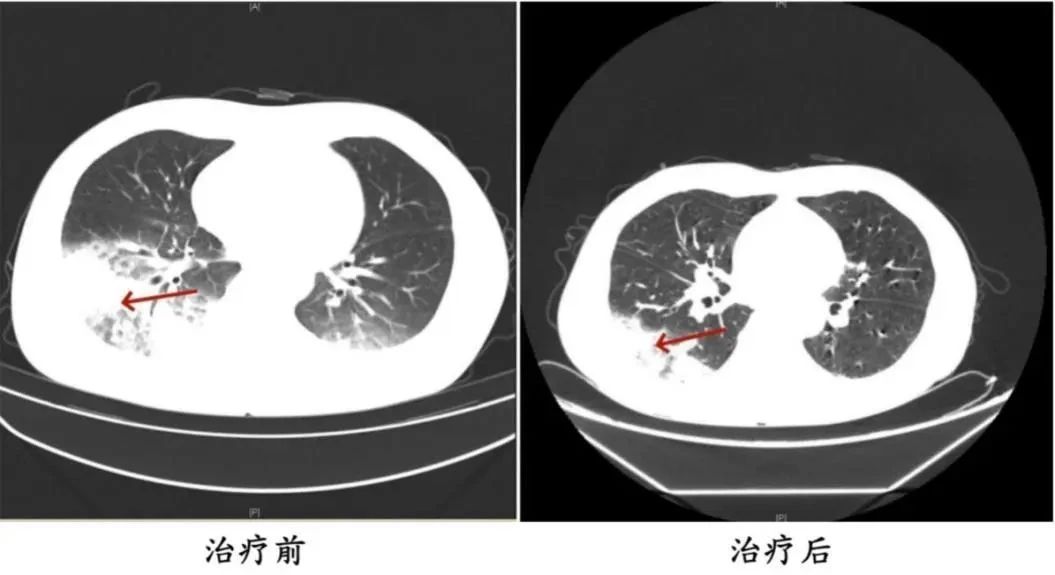

医生询问发现,周先生此前驾车出差,因为天气热,他启动了久未清洗的车载空调,每天在车上的时间超过十个小时,回来后就出现了如上症状。经过检查,最终确诊为军团菌肺炎。

周先生治疗前后的肺部CT影像